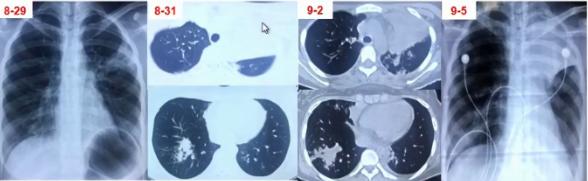

图2 影像表现以多发肺结节合并晕征,类似于真菌感染

图3 双肺弥漫性小结节为主,中下肺布满粟粒样小结节,部分融合成片状

图4 患者肺部CT表现

图5 影像学表现为实变